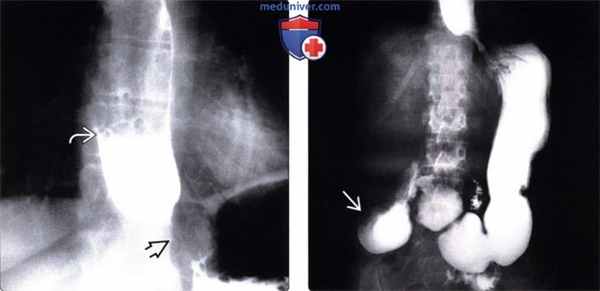

(Слева) На рентгенограмме, выполненной во время рентгеноскопии верхних отделов ЖКТ, определяется гастроэзофагеальный рефлюкс вследствие «зияния» нижнего пищеводного сфинктера. Первичная перистальтика пищевода отсутствует. Это относительно ранние изменения при склеродермии: ни стриктуры, ни язв еще не возникло.

(Справа) На рентгенограмме, выполненной этому же пациенту в положении лежа на спине во время рентгеноскопии верхних отделов ЖКТ, определяется обратный заброс бариевой взвеси в расширенный пищевод.